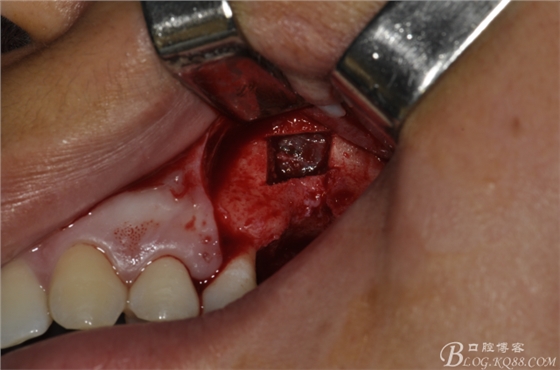

術(shù)前X片。上頜竇外提一例

術(shù)前口內(nèi)照片。上頜竇外提一例

術(shù)中照片。

超聲骨刀切開骨外板 上頜竇外提一例